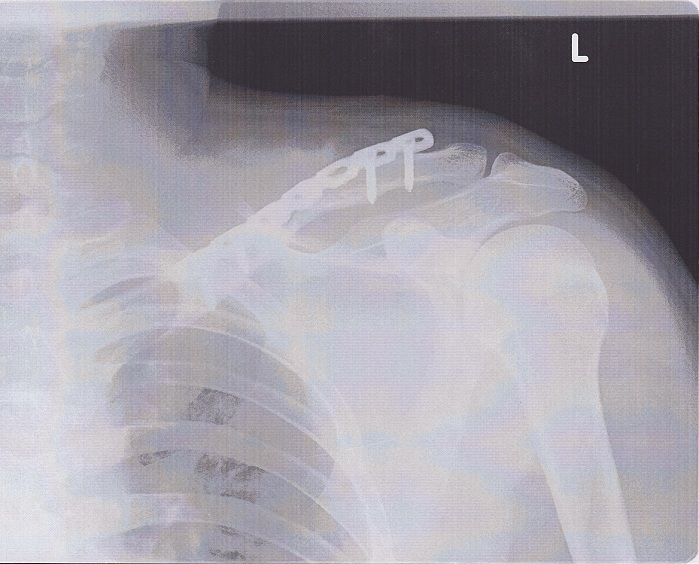

手術後

プレートとネジ4本で固定。

どうみても、ホームセンターで売ってるとしか見えない。

小さい骨片はどこへやら。

グーグル先生に調べたら、プレートに細いワイヤで巻きつける例があるらしいが。

指で鎖骨を伝うと、出っ張っていた骨が正常な位置に戻っているのがわかる。

そのまま肩に向かって指を伝わせると、明らかに人工物の感触が。。。

明らかに手術前後と比べると痛み方が違う。

特に三角巾を外した状態では腕の重みに肩が耐えられず激痛が走っていたのに対し、

その手の痛みはほぼ皆無になた。